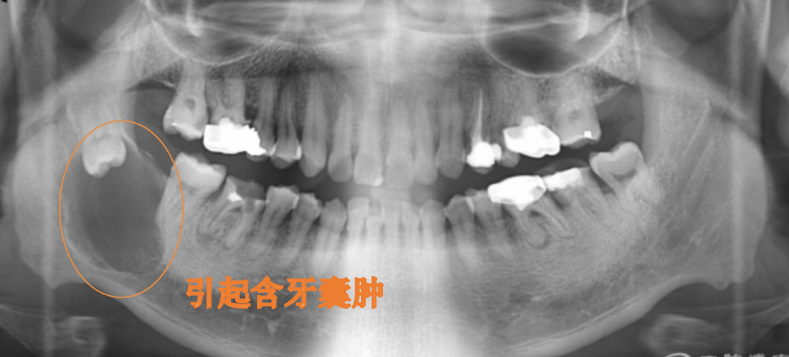

随着人类的饮食的精细,颌骨逐渐变小,而牙齿大小没有明显变化,这就导致了牙量大于骨量,所以智齿因为生长空间的受限往往萌出受阻或异位生长,甚至还会挤压前面的第二磨牙,这就会造成智齿区牙龈肿痛、邻牙损伤,颞颌关节病,并成为牙源性囊肿及肿瘤、面部肿胀、面部间隙感染、张口受限等不适症状,严重的可能会引起发烧等全身症状。

拔:引起牙源性囊肿和肿瘤。